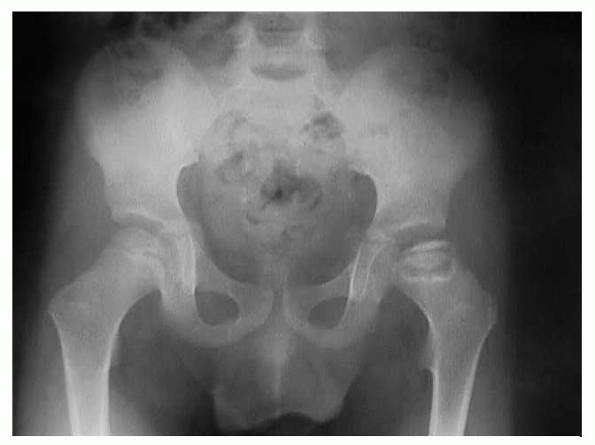

Fragmentation and flattening of head (Fig. 6-2)

![]() |

Figure 6-2 Flattening and sclerosis of the femoral head in Perthes disease.